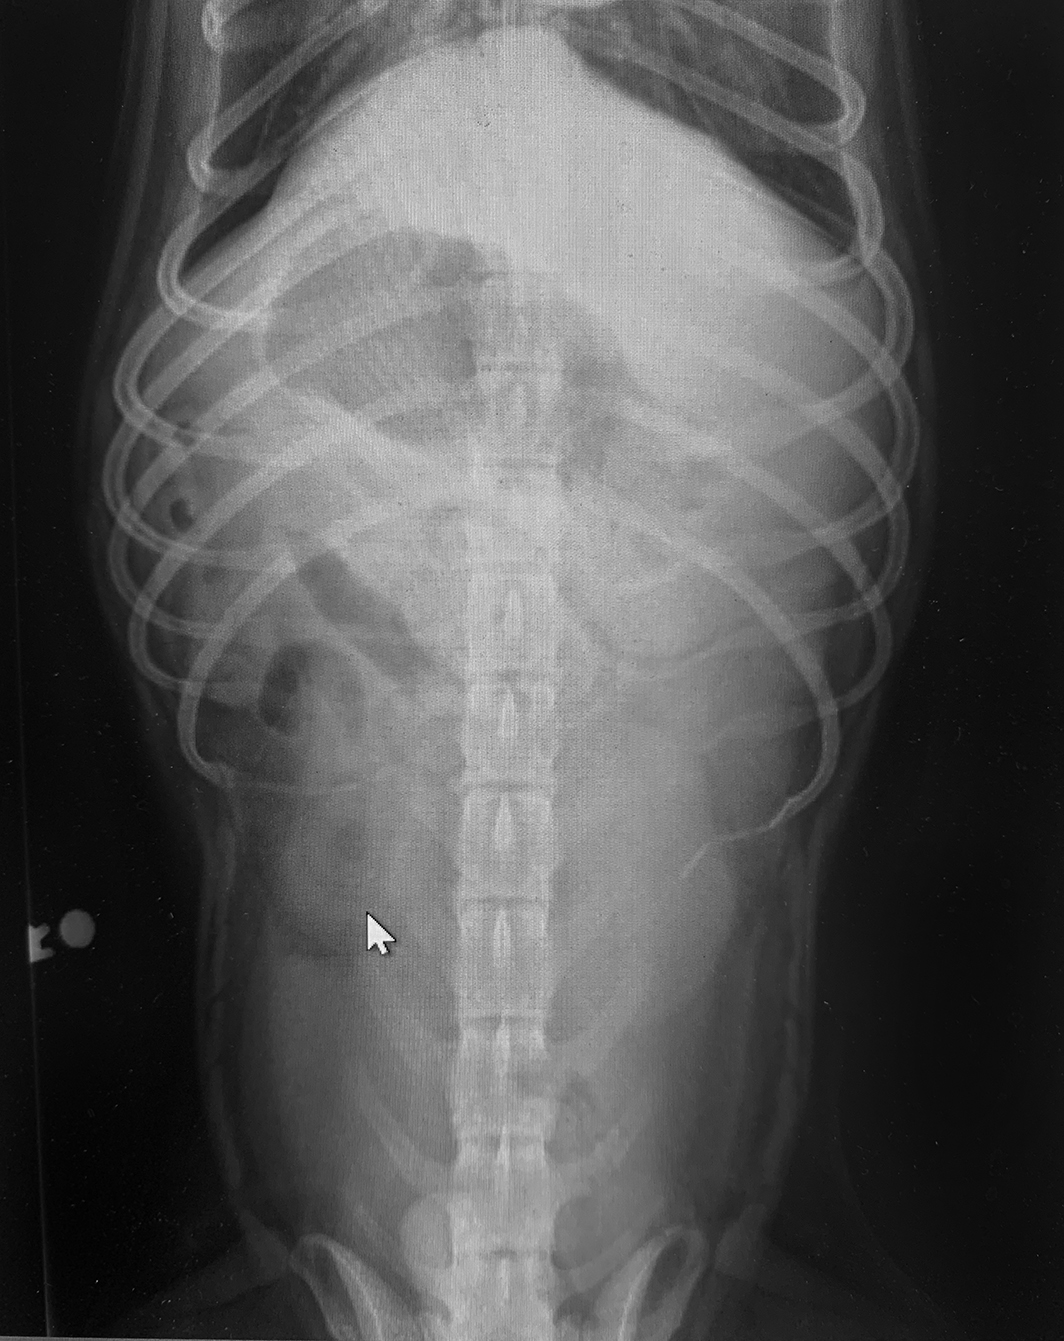

At the veterinarian’s, his bloodwork is all normal, but his x-rays show huge loops of gas-distended bowel. This classic case is a slam dunk – an easy diagnosis. Usually, with immediate surgical intervention, the happy, healthy dog will be back in no time.

Interpreting symptoms of a blockage can be challenging, but ironically, it can be even more difficult to interpret the diagnostic x-rays. Many materials ingested by dogs do not show up on x-rays. Anything cloth or plastic can be difficult or impossible to see. Partial blockages don’t cause the classic gassy distention of the intestines that happens with full blockages. Your vet may recommend repeating the x-rays in 24 hours if there is a suspicion of partial or full obstruction. Looking for changes (or lack thereof) on x-rays can be informative.

An otherwise healthy 5-year-old dog came into the veterinary clinic with a history of several days of intermittent vomiting and not feeling well. Initial x-rays were inconclusive, showing no obvious foreign material and no gas-distended bowel. He was treated for non-specific gastroenteritis and sent home.

Over the next week, the dog continued to vomit intermittently, had a decreased appetite and weight loss, and produced only small amounts of stool. His blood test results were all normal. Repeat x-rays were still unimpressive as far as gas distention of his bowel, but the offending foreign body could finally be seen. At surgery, a hard plastic hexagon-shaped object was removed from the small intestine where it was lodged. The hole in the center of the object allowed the contents of the intestines to pass through, thereby preventing a more easily diagnosed full blockage. He should experience a full and smooth recovery.